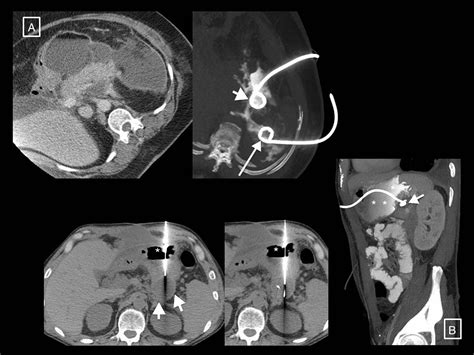

Diagnosing necrotizing pancreatitis typically requires advanced imaging. Contrast-enhanced Computed Tomography (CECT) is the gold standard for identifying areas of the pancreas that do not "enhance" or light up with dye—a hallmark sign of dead, non-perfused tissue. Magnetic Resonance Imaging (MRI) is also utilized for patients who cannot tolerate the contrast dye used in CT scans or for those with impaired kidney function.

Managing the causes and the condition itself requires a multidisciplinary approach. The primary goal is to support organ function and prevent infection. If the necrotic tissue becomes infected, surgical intervention—such as necrosectomy—or minimally invasive drainage procedures become necessary. Antibiotics are generally reserved for confirmed infections rather than as a preventive measure, as prophylactic use can lead to resistant bacterial strains.